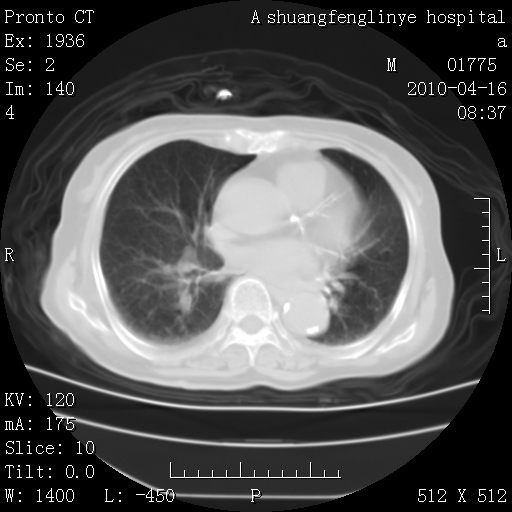

标题: CT25784:咳痰、请会诊!结核?

陈旧性结核,胃腔扩大,脾脏受压后移

考虑左肺上叶增殖灶、纤维灶。

支持结核

慢支肺气肿,左上陈旧性结核,主动脉冠脉钙化

1)左肺上叶结核(纤维、增殖病灶)。2)冠状动脉及主动脉钙化。

1)左肺上叶结核(纤维、增殖病灶)。2)冠状动脉及主动脉钙化。肺动脉高压